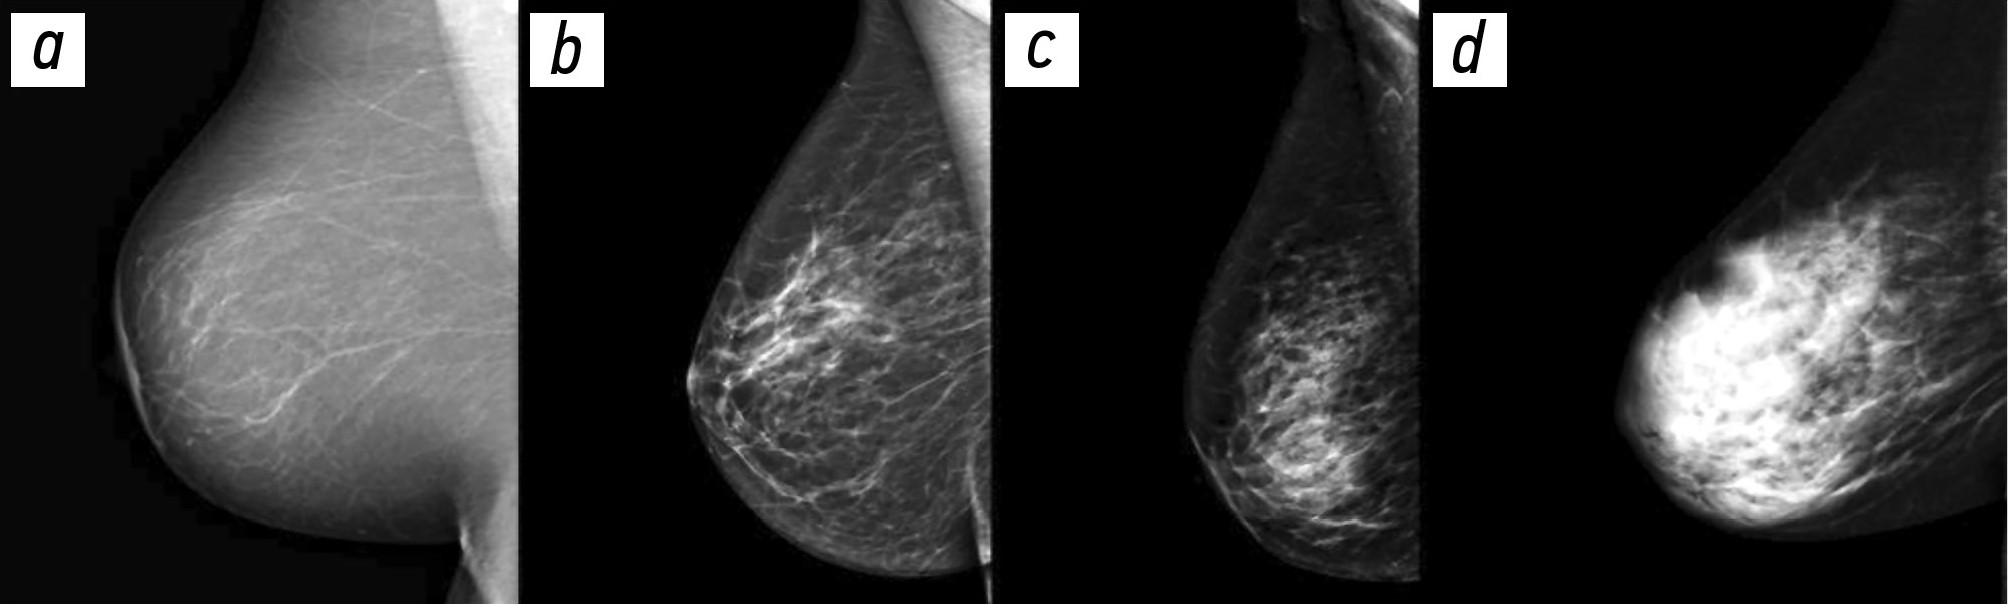

В данном проспективно-ретроспективном исследовании был проведен анализ результатов маммографического исследования 1030 пациенток, проходивших диспансеризацию в Университетской клинике МНОИ МГУ имени М.В.Ломоносова в период с 2019 по 2023 год. Для адекватной трактовки результатов инструментальной диагностики РМЖ была использована система BI-RADS (Breast Imaging Reporting and Data System). Оценка плотности молочных желез проводилась на основании шкалы, разработанной Американским колледжем радиологии (англ. – ACR - American College of Radiology) [9]. Согласно этой шкале, выделяют 4 типа молочных желез (Рис.1):

А – МЖ практически полностью жировой плотности (термин "плотность" здесь и далее в данном контексте характеризует степень ослабления рентгеновского излучения при прохождении через ткань молочной железы). Маммография обладает высокой чувствительностью.

В - Отдельные участки фибро-гландулярной (фиброзно-железистой) низкой рентгенологической плотности.

С - МЖ неоднородной (гетерогенной) высокой плотности, либо отдельные участки молочных желез достаточно плотные и могут скрывать небольшие образования.

D - Очень плотные МЖ. Маммография обладает низкой чувствительностью.